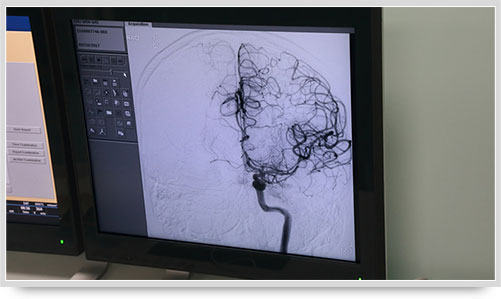

弓上造影、超选到颈内动脉、椎动脉......在数字减影技术下,注入显影剂后,导管经患者右侧股动脉在体内推进,由于股动脉离脑血管距离较远,中间“路程复杂”,对施术医生的要求非常之高。

同时,手术台前的液晶显示仪屏幕上清晰地现显出导管的路径,在李主任的操作下准确到达指定检查部位,各条血管的“庐山真面目”清晰可见。